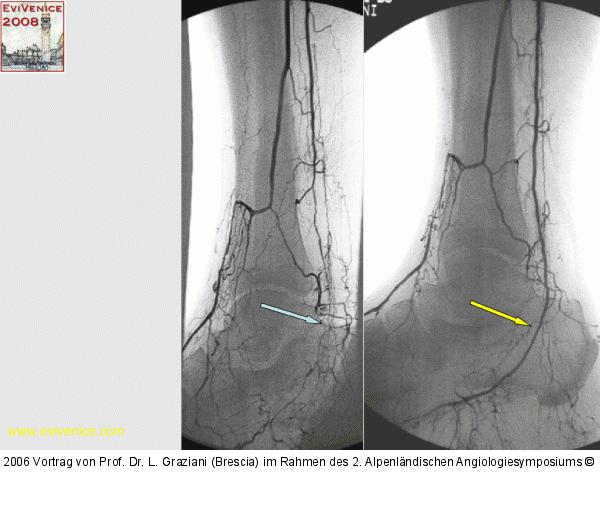

Vortrag von Prof. Dr. L. Graziani (Brescia) im Rahmen des 2. Alpenländischen Angiologiesymposiums

PTA of the foot arteries in diabetics: Extremities Extreme Angioplasty

Abbildung 22: Revaskularisation